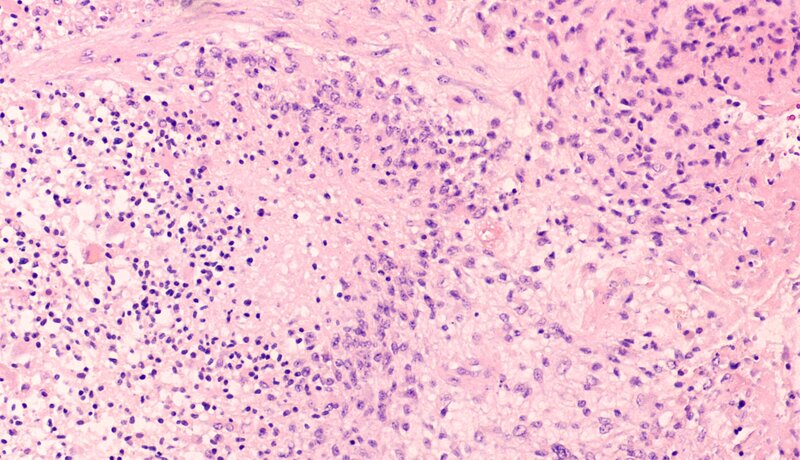

Allerdings sind seit vielen Jahren in der Wissenschaft Studien bekannt, wonach bestimmte Zellen des Gehirns körpereigene Cannabinoide ausschütten - die auch zur Selbstverteidigung gegen Glioblastome dienen. Das Glioblastom ist der häufigste und zugleich bösartigste Hirntumor, an dem allein in Deutschland jährlich etwa 4.000 Menschen erkranken. Etwa die Hälfte der Patienten überlebt vom Zeitpunkt der Diagnose gerechnet durchschnittlich nur 16 Monate. Neue Behandlungsformen sind deshalb dringend nötig.

In diesem Wissen und motiviert von den vorangegangenen Studien, haben die Forscher/-innen nun den Effekt von CBD gegen Tumorzellen aus Mäusen und Menschen getestet. Die Zellen wiesen etliche Mutationen auf, die für Glioblastome typisch sind. Resultat: Binnen zwei bis drei Tagen nach Gabe des Cannabidiols sterben diese Glioblastomzellen ab. „CBD induziert den Zelltod bestimmter Glioblastome, es gibt aber auch Tumore, die nicht therapeutisch auf CBD ansprechen“, sagt Glaß. Außerdem haben die Forscher/-innen ermittelt, „dass CBD einen Signalweg blockiert, der ansonsten Entzündungsreaktionen kontrolliert.“ Die Tumorzellen nutzen diesen Signalweg, um immer weiter zu wachsen. Glaß‘ Team hat zudem einen „Marker“ gefunden, der anzeigt, welche Glioblastome höchstwahrscheinlich auf CBD ansprechen werden und welche nicht.